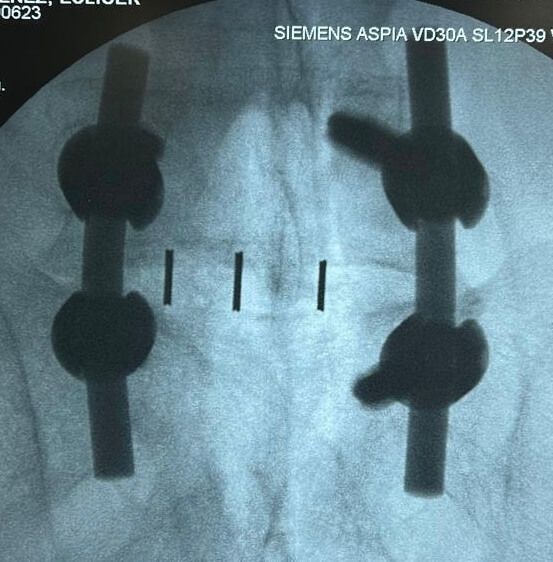

Cirugía de mínima invasión de columna vertebral

Realiza cirugías endoscópicas mínimamente invasivas de columna.

Cirugía de Columna

Realiza cirugía habitual y endoscópica mínimamente invasiva de columna vertebral.